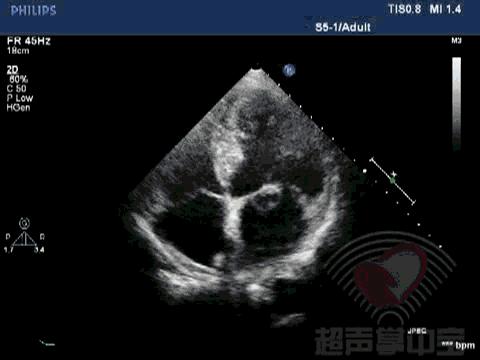

二尖瓣充血性囊肿,二尖瓣血性囊肿是什么意思 动态图2:四腔心切面显示该囊状物质软,有形变,二尖瓣开放正常